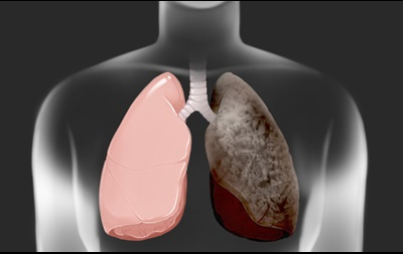

폐암 예하는방법

흡연을 하지 않아도 폐암을 취하는 경우가 있습니다만, 이러한 상황을 막기 위한 방법중의 하나, 우선 요리를 할 때는, 연기가 나는 음식을 할경우 실내에서 조리를 할때 환기를 하고 공기를 순환시키는것이 중요 합니다 . 그리고 조리 하는방법으로는 굽거나 튀기는 것보다 쪄서 조리하는 것이 좋습니다 . 그리고 구울 때 탄음식이 되지 않도록 조심해주세요 . 음식이 타면 발생하는 유해 물질이 있지만, 그것을 흡입한다면 폐암의 원인이 될 수 있습니다 .